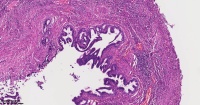

炎性息肉?潴留囊肿?腺体是否有问题?

性别

女

年龄

51岁

临床诊断

一般病史

宫颈赘生物

标本名称

大体所见

息肉。

稳妥起见最好做一做免疫组化。